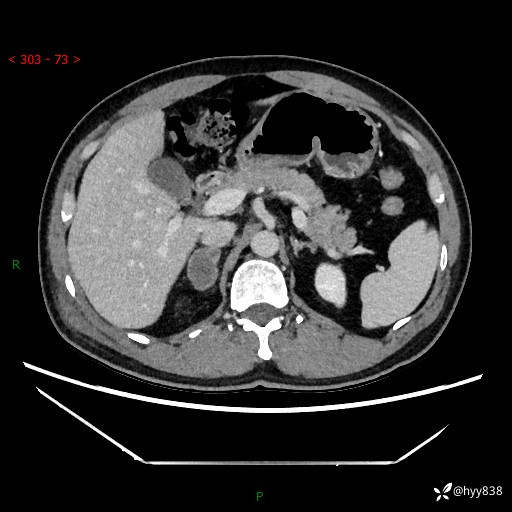

现病史:患者9月4日摔伤在深圳市宝安区中心医院行CT检查提示右侧肾上腺区结节(38*27mm),复查B超提示右侧肾上腺区可见一61*24mm异常低回声团,建议进一步检查。进一步完善增强CT后提示:右侧肾上腺区肿块及周围渗出改变,大致同前,考虑肾上腺腺瘤,不除外瘤内出血可能,否认阵发性头晕、头痛、出汗、乏力等不适,门诊以“ 右侧肾上腺肿瘤”收入住院。 起病来,患者精神、食欲、睡眠可,大便通畅,小便如上述,体力体重无明显改变。

肾上腺CT平扫

增强(动脉期+静脉期)